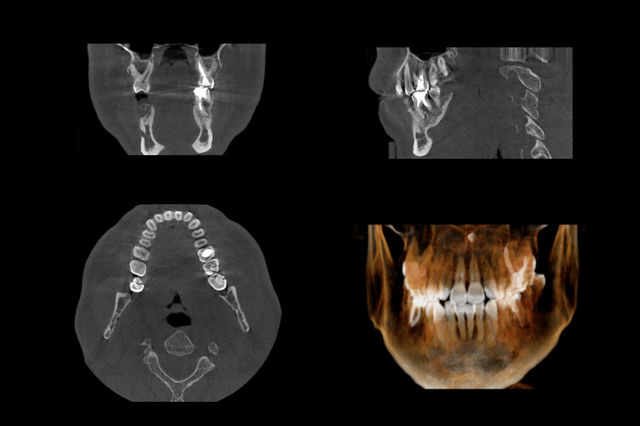

Set of MRI scanner slices of dental part of adult human male scull with multiple problems on white background.